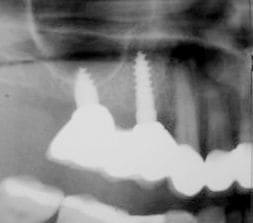

je voulais parler de ce fact pour les implants courts:minimum 4mm os vertical peut suffire (pour eviter un sinus lift externe de tatum) . dans ma pratique depuis quelques années je vois que ca marche , quelques cas cliniques des années passées.

j´ai oublié : 4mm plus 2mm( gagnés par un sinus lift interne)

Le plus important dans un implant sont les 4 premiers millimètres crestales ( c'est pourquoi de nombreuses industries, NB, astra,Bio horizon... ont chosit de faire des implants avec des micro fissures crestales pour augmenter la surface sur ces premiers millimètres et garantir une meilleure stabilité 1aire et 2aire).La partie dans l'os spongieux est moins décisive. Dans un contexte comme celui ci le platform switching est un facteur à ne pas négliger.